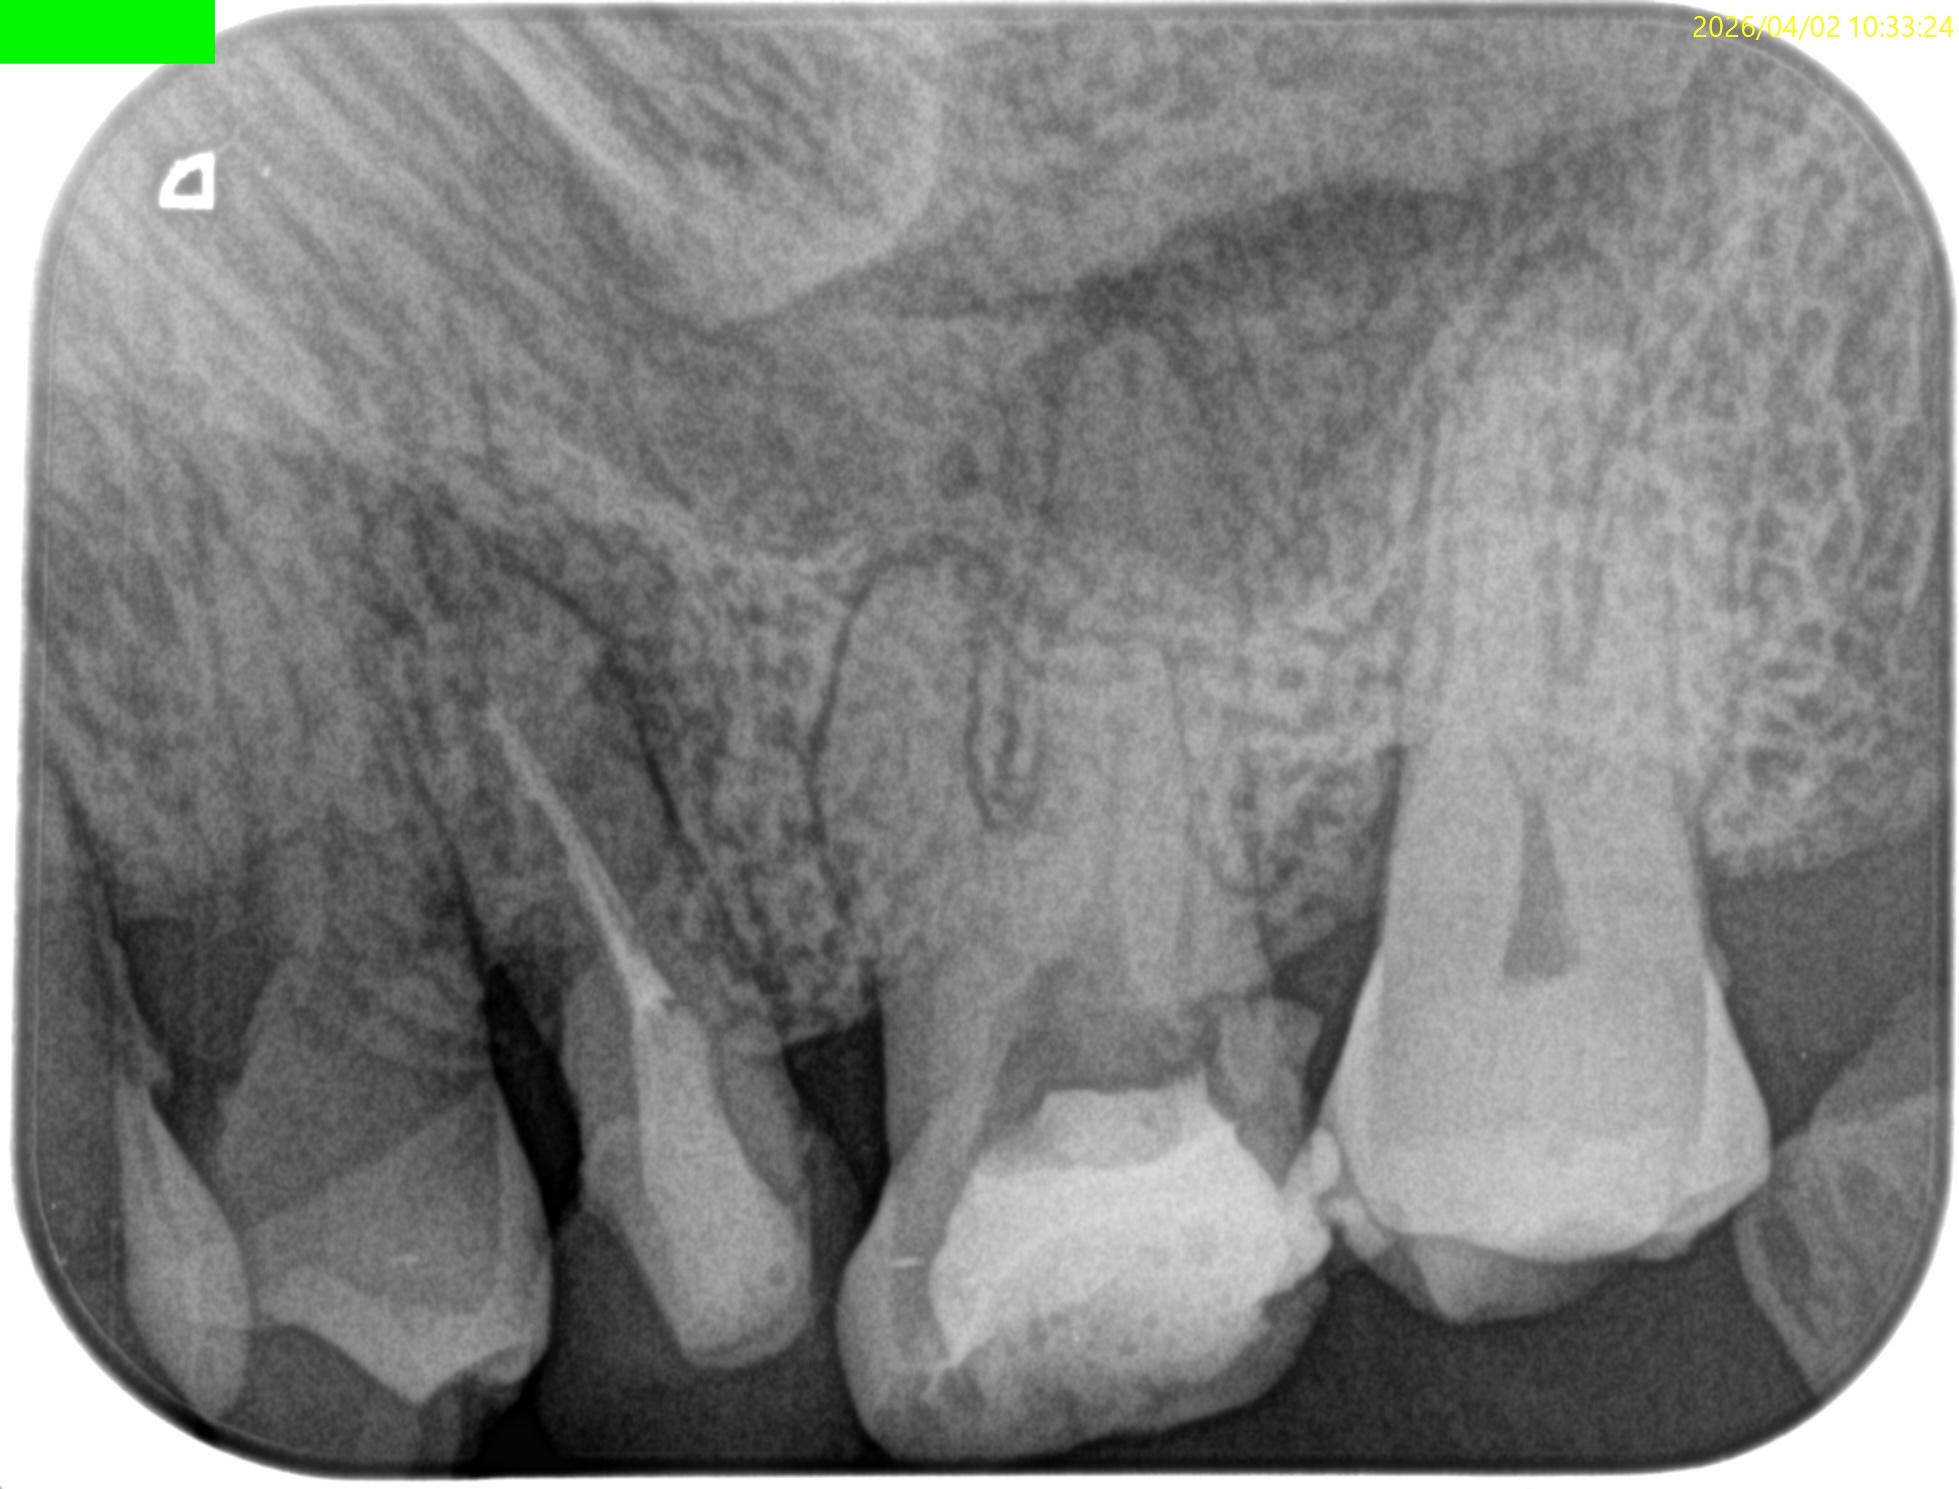

Pre-op Endo test(2026.4.2)

このPA2枚でみても、東京の歯科医院の担当者は根管口さえ発見していないという臨床的事実がわかる。

さておき、#13にも病変があるのがわかるので#13も分析した。

#13

#13は#14よりも大きな根尖病変がある。

ここも治療が必要だろう。

Pulp Dx: Previously initiated therapy

Periapical Dx: Symptomatic apical periodontitis

Recomended Tx: Re-RCT

では、再根管治療が必要な治療とわかるのだが、その成功率はどれくらいか?と言えば

穿通できれば86%

穿通できなければ60%

である。

おおよその作業長が類推できる。

が、いずれにしてもこの治療での最大のポイントになるのはMB2がどこにあるか?である。

MB2の根尖部にはCBCTで根尖病変があるからだ。